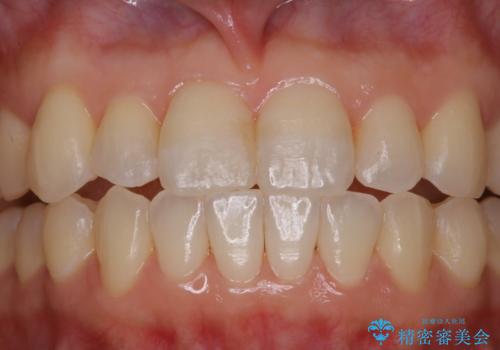

矯正治療とセラミック治療が終了後のPMTC

- 矯正治療とセラミック治療の総合治療が終了したため、クリーニングをしっかりとしてからメンテナンスに入りたいとのことでした。PMTC30分コースを行いました。

矯正治療が終わり、せっかくきれいになった歯並びも、虫歯・歯周病などになってしまっては元も子もありません。

矯正治療やセラミックなどによる被せ物の治療終了のタイミングではクリーニングを行い、汚れや着色の除去、歯と歯の間・歯と歯肉との境目などのケアをしっかりすることをおすすめしています。

ご自身での歯ブラシ・セルフケアを行うと同時に、定期的なクリーニング(PMTC)を行うことで、いつまでも健康な歯を保つことができます。